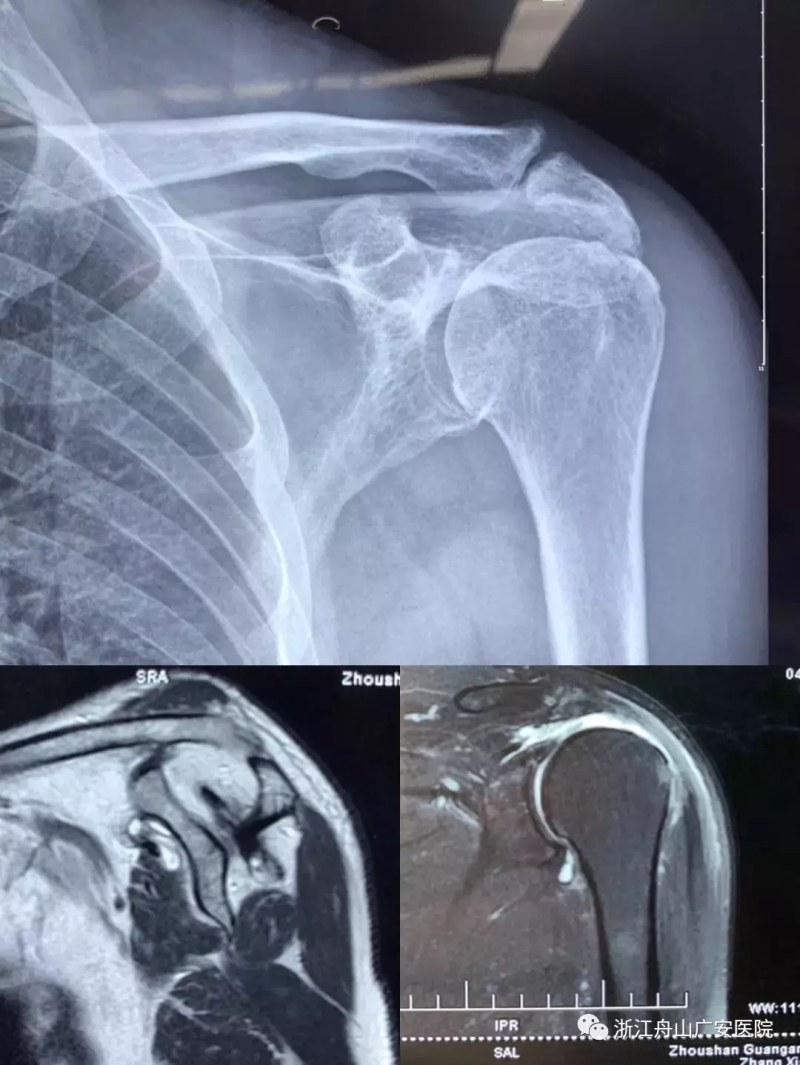

張大伯一年前因右肩巨大肩袖斷裂,曾在我院行關(guān)節(jié)鏡微創(chuàng)手術(shù),術(shù)后恢復(fù)非常滿意?,F(xiàn)患者要求進(jìn)一步行左肩關(guān)節(jié)手術(shù)治療入院,經(jīng)過廣安醫(yī)院常務(wù)副院長危立軍、關(guān)節(jié)科及運(yùn)動(dòng)醫(yī)學(xué)科羅軍主任的詳細(xì)檢查,患者為左肩巨大不可修復(fù)肩袖撕裂關(guān)節(jié)病,肩袖的脂肪浸潤達(dá)到四級,常規(guī)的微創(chuàng)手術(shù)治療不能恢復(fù)患者的肩膀功能,只能通過特殊類型的人工肩關(guān)節(jié)——反式全肩人工關(guān)節(jié)來重建關(guān)節(jié)功能。

反式肩關(guān)節(jié)置換術(shù)后照片